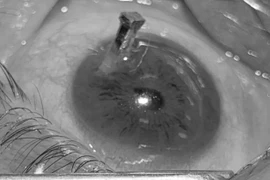

Thái Nguyên cấp cứu, xử trí ca chấn thương mắt phức tạp do tai nạn lao động

Bệnh nhân 32 tuổi bị chấn thương mắt phức tạp sau tai nạn lao động vừa được Khoa Mắt, Bệnh viện Trung ương Thái Nguyên phẫu thuật cấp cứu thành công.